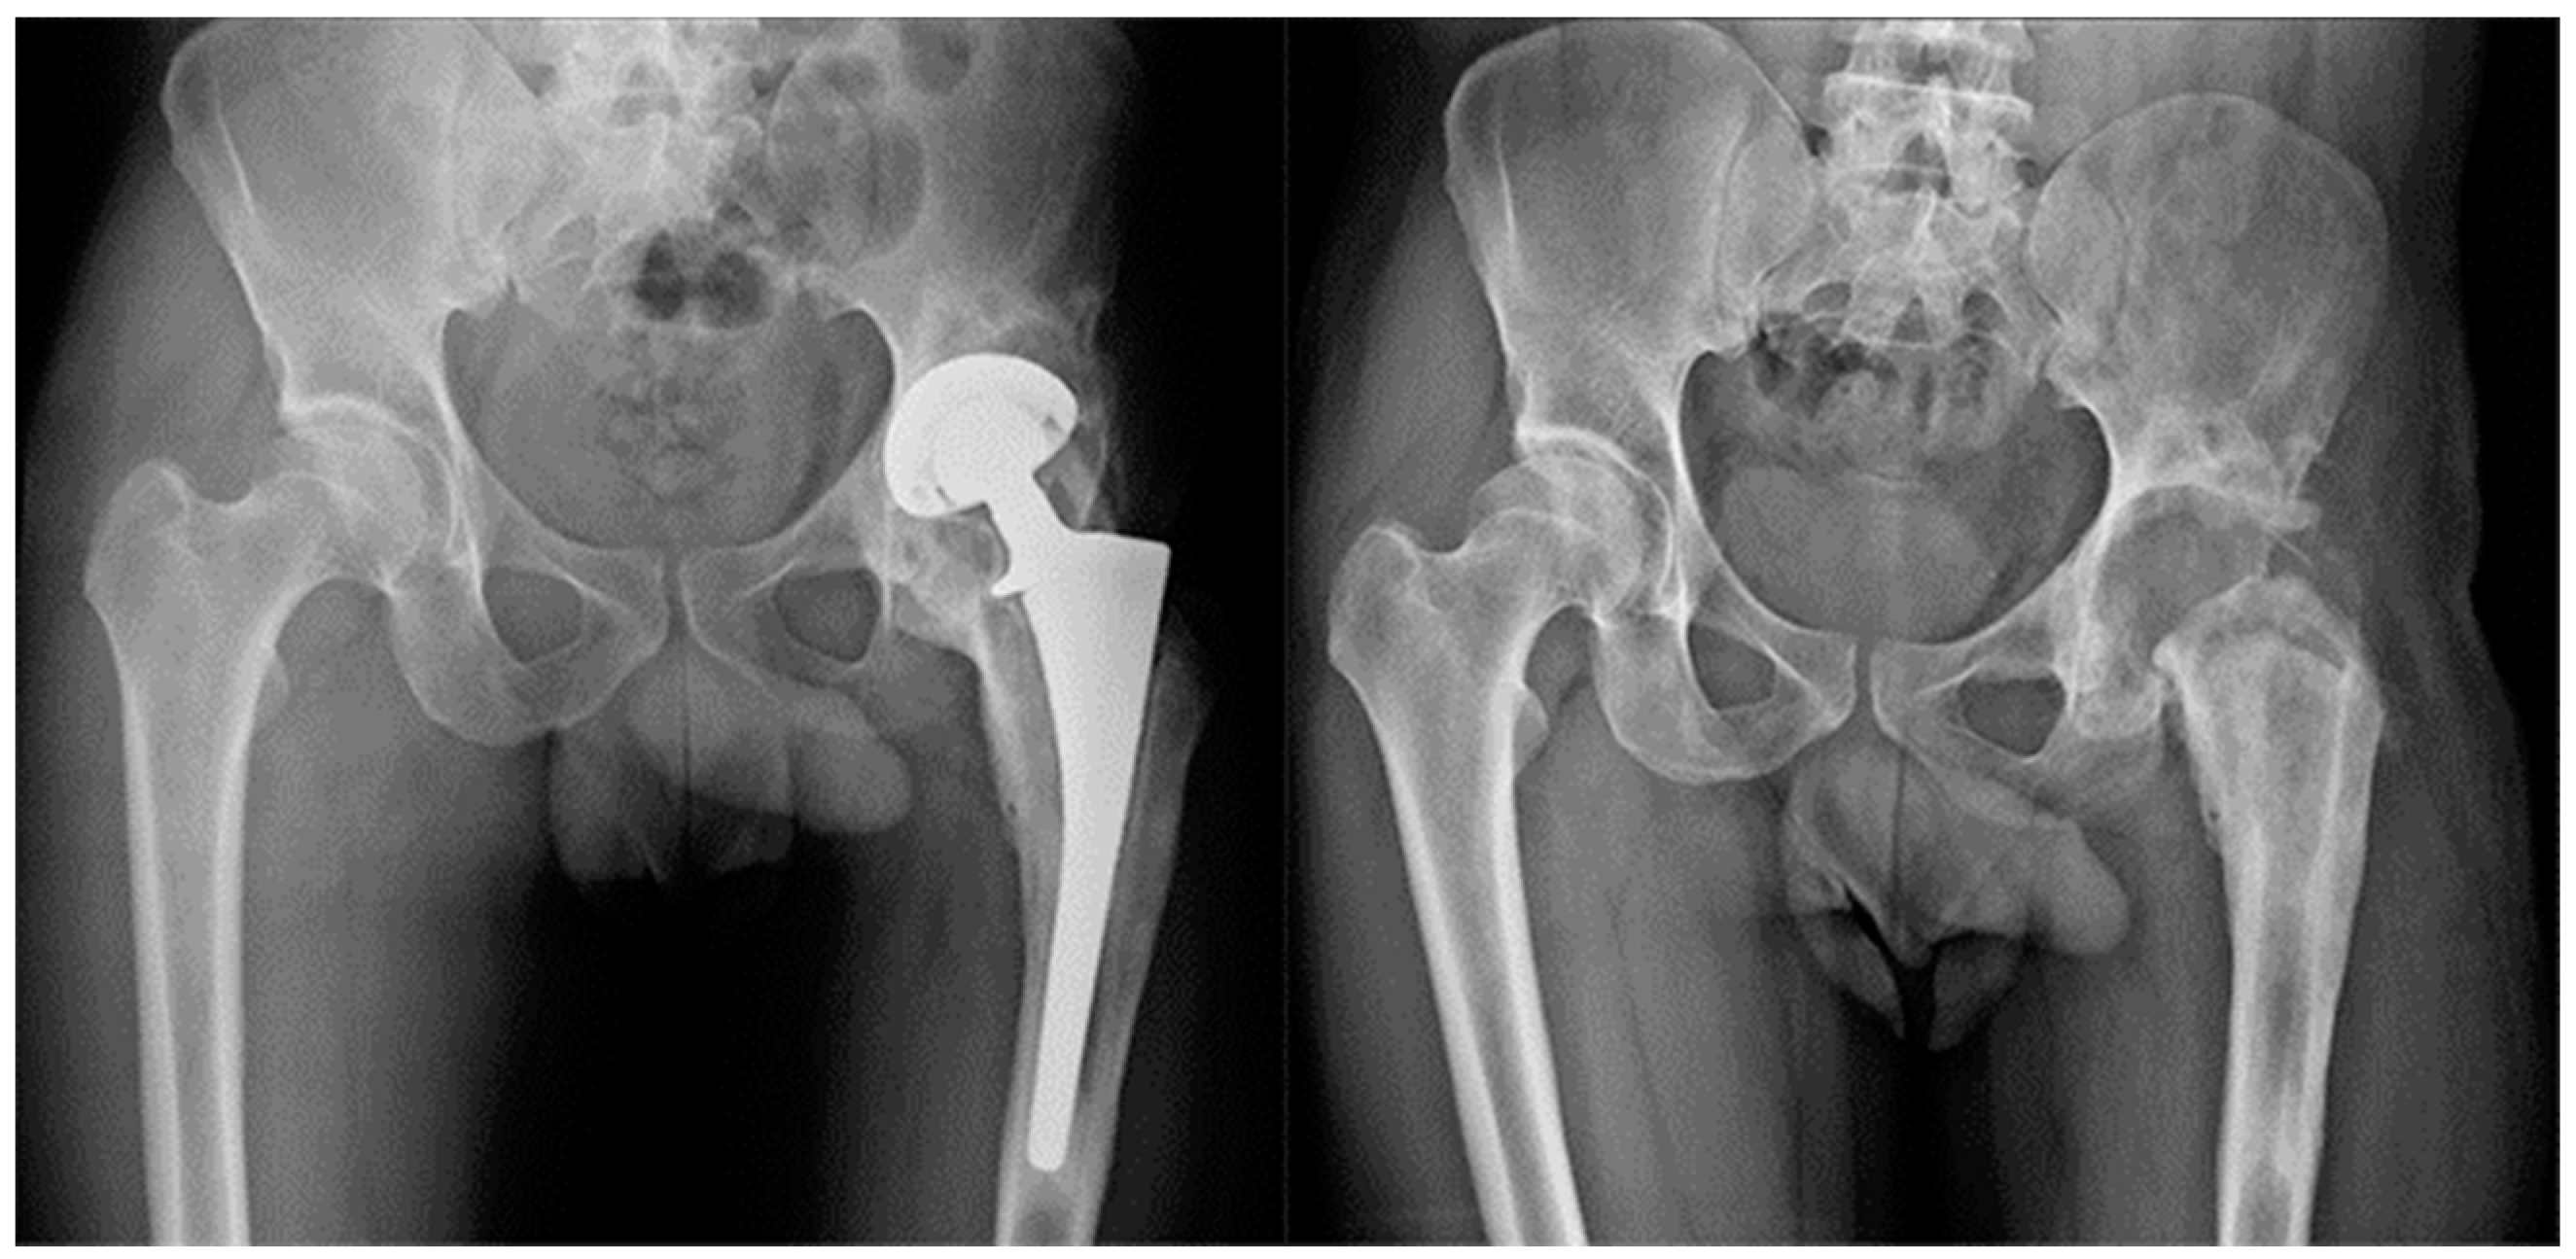

The same procedure was performed in all patients. Patients were explanted and antibiotic therapy was subsequently set up, at first empiric, and then targeted for the isolated pathogen. In no case were antibiotic spacers used. The antibiotic therapy was administered according to the culture sensitivity results. Antibiotic therapy was performed until normalization of CRP following explantation and, in any case, never for more than 8 consecutive weeks. One year after resection arthroplasty was performed, the following two possible outcomes were evaluated: successful TSE arthroplasty was performed in 14 patients (Group A) (Figure 1), and resection arthroplasty without reimplantation in 7 (Group B) (Figure 2). The following were the replanting criteria: CRP normalization with antimicrobial treatment in at least two controls separated by two weeks. If normalized, antibiotic therapy was discontinued, patients were then monitored for an additional 4 weeks by weekly CRP checks. If the latter remained normal, labeled leukocyte scintigraphy was done. If the latter was also negative, reimplantation was scheduled, which was to be performed only after intraoperative negative histology.

Figure 1.

Group A Patient affected by chronic PJI treated with TSE. The patient was eligible for reimplantation after 4 month targeted antimicrobial therapy. After 12 months follow up there were no signs of recurrence of infection.